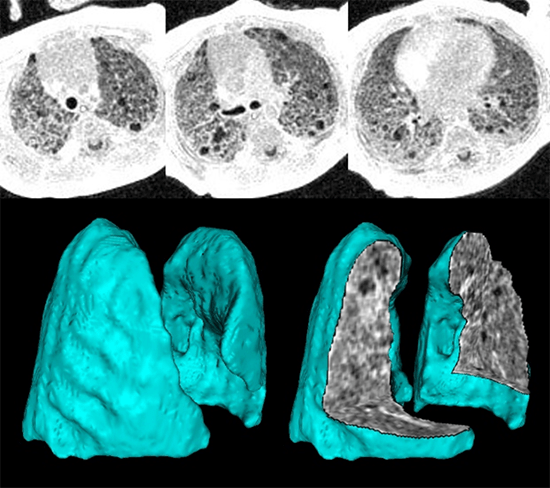

Imaging of Regional Lung Ventilation in Infants

We aim to create novel imaging-based phenotyping of lung ventilation abnormalities in neonatal lung disease by employing pulmonary MRI with proton-density weighting and self-navigated gating, thus providing dynamic quantification of the 3D structure during free-breathing. Neonatal diseases of interest include bronchopulmonary dysplasia (BPD, otherwise known as chronic lung disease of prematurity) and pulmonary hypoplasia (underdeveloped lung tissue, frequently seen in congenital disorders such as congenital diaphragmatic hernia, CDH). The underlying lung abnormalities, their relationship to outcomes, and response to clinical care management is often poorly understood in patients with these conditions.